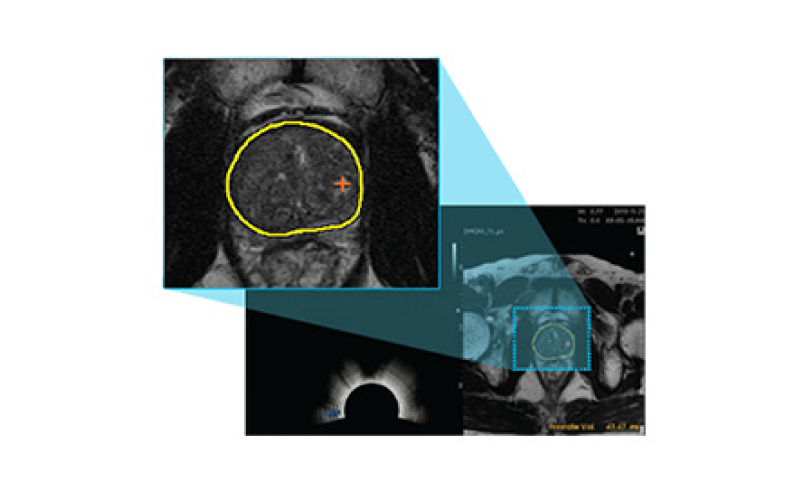

전립선을 자동으로 분석해 경계 분할

3D 영상

병변 정확 탐지